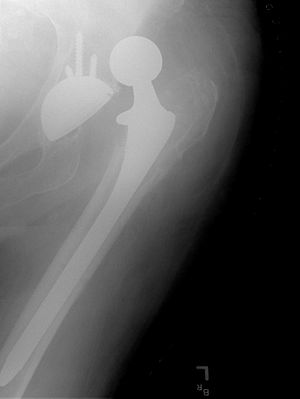

صورة بأشعة إكس، مفصل المريض (يسار الصورة) تم استبداله، with the ball of this ball-and-socket joint replaced by a metal head that is set in the thighbone or femur and the socket replaced by a white plastic cup (clear in this X-ray). Pelvic anatomy consistent with that of a female (large infrapubic angle, large pelvic opening). | |

استبدال مفصل الورك Hip replacemen، هي عملية جراحية يتم فيها استبدال مفصل الورك بمزورعة طبية صناعية. يمكن أن تجرى جراحة استبدال مفصل الورك كاستبدال تام أو نصفي. تهدف هذه الجراحة بشكل عام إلى إزالة ألم التهاب المفصل أو لإصلاح تخرب المفصل الفيزيائي كجزء من علاج كسر مفصل الورك. يتألف استبدال مفصل الورك التام (رأب مفصل الورك التام) من استبدال كل من الحق acetabulum ورأس الفخذ في حين يستبدل بشكل عام في تصنيع المفصل النصفي (رأب المفصل النصفي) رأس الفخذ فقط. تعتبر عملية استبدال مفصل الورك حالياًً عملية الجراحة العظمية الأكثر نجاحاً و موثوقيةً حيث أبدى 97% من المرضى تحسناً ملحوظاً.